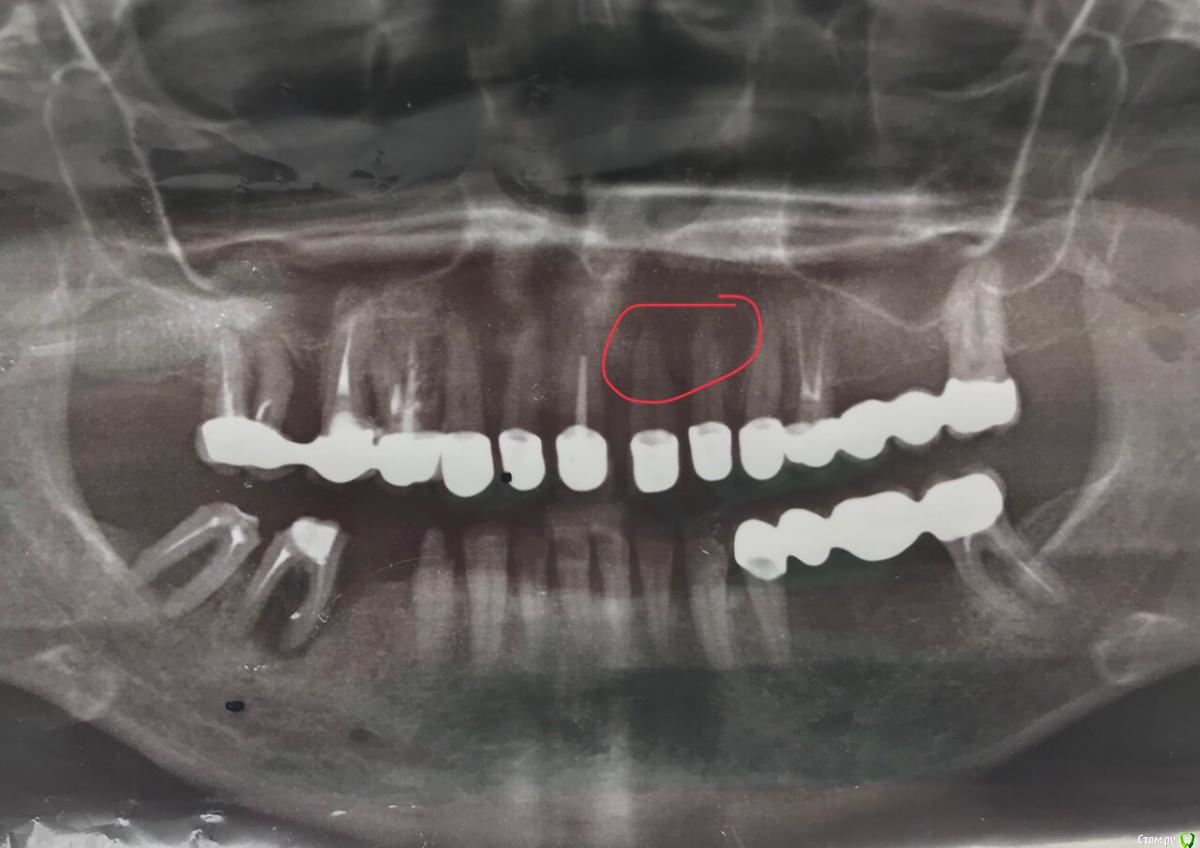

dr.Dre Опубликовано 7 апреля, 2018 Поделиться Опубликовано 7 апреля, 2018 (изменено) Добрый день коллеги , пациентка 45 лет прийшла с проблемой что 21 зуб выступает, есть проблемы с щитовидной железой тут явный парадонтит, скажите пожалуйста есть ли смысл сделать открытый кюретаж в области 21 с подсаткой кости ? 47,48 планируеться удалить поставить имплантанты.Читал что такая резорбция кости может быть повязанная с щитовидной, не является ли противопоказанием к имплантации? Изменено 7 апреля, 2018 пользователем dr.Dre Ссылка на комментарий

Nazim_NV86 Опубликовано 8 апреля, 2018 Поделиться Опубликовано 8 апреля, 2018 Так пробелы или проблемы?Тс.. то что вы обвели на панораме означает что в этом месте панорама темнее. И не несёт диагностической ценности. Делать НКР я на вашем месте не стал бы. Максимальная санация. Ссылка на комментарий